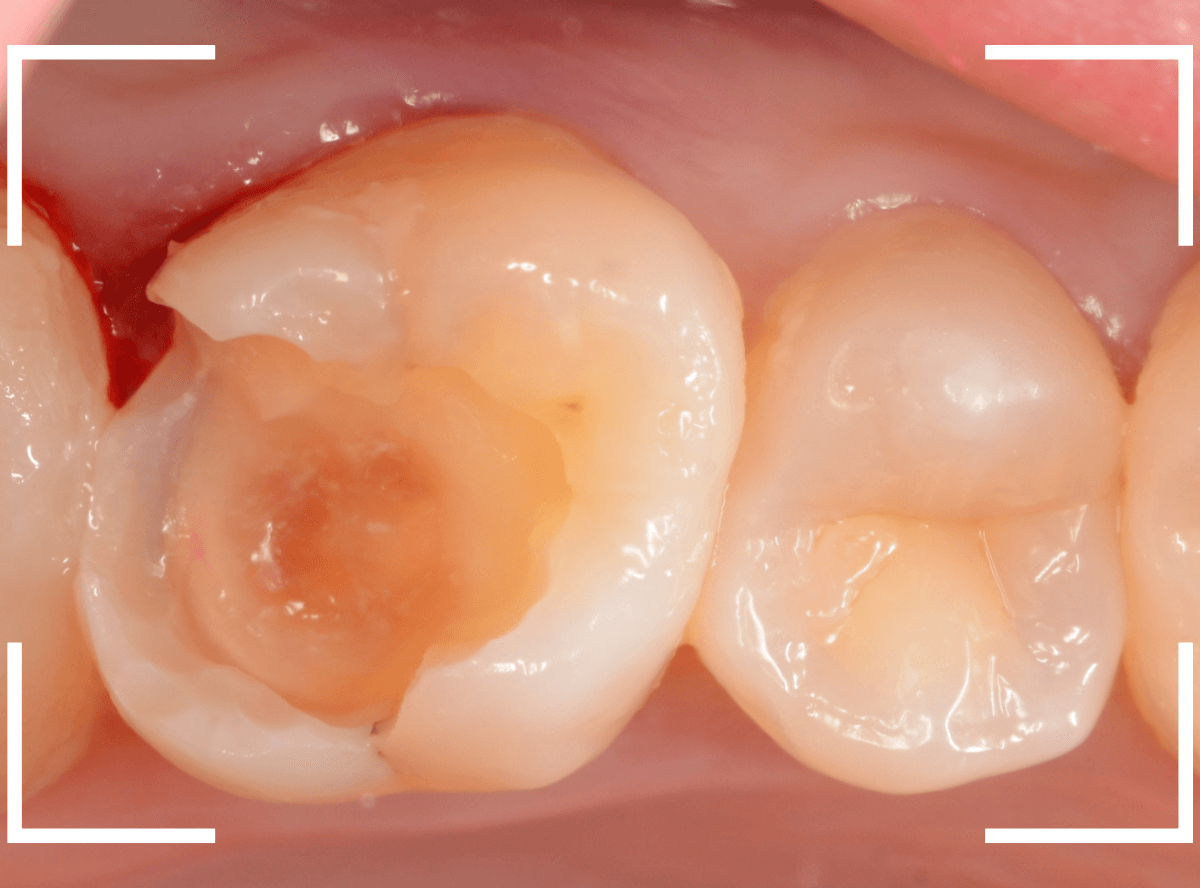

Case.28 虫歯治療後、半年以上来院されなかった患者さん

虫歯を治療して、セメントで歯を削った部分を封鎖した後、再修復を検討中で、半年以上来院されなかった患者さんです。

虫歯を治療して、セメントで封鎖した状態というのは、家でいえば、しっかりした屋根がない状態です。

今回は、セメントの一部がはがれる程度で済んでいましたが、虫歯が再発し、再治療、最終修復物の変更の可能性も出てきます。

皆さんも治療は中断せずに最後まで通院するようにしてくださいね。

治療再開後、セラミックの最終修復を希望されましたので、歯をトリミングし、型取りします。